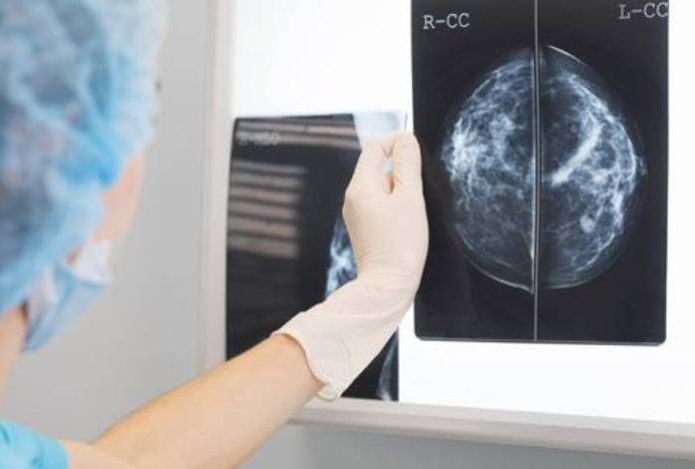

Скрининг на рак молочной железы могут проходить женщины от 40 до 70 лет через каждые два года. Его проводят с использованием маммографии в двух проекциях. Далее в случае необходимости — УЗИ, прицельной маммографии, биопсии.